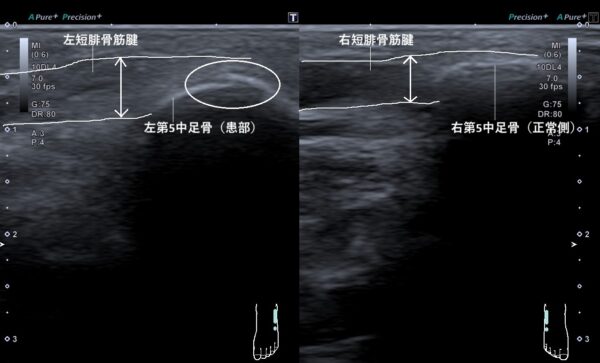

それから、超音波画像観察を行うと第5中足骨基部の骨膜が剥離損傷していました(画像、丸の中の白い線が二重に重なっている箇所)。

また、第5中足骨基部に付着している短腓骨筋腱が腫れて太くなっていました(画像、矢印の長さの比較)。